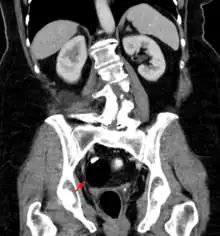

Beyond the newborn period, symptoms of a teratoma depend on its location and organ of origin. Ovarian teratomas often present with abdominal or pelvic pain, caused by torsion of the ovary or irritation of its ligaments. A recently discovered condition where ovarian teratomas cause encephalitis associated with antibodies against the N-methyl-D-aspartate receptor antibody (NMDAR) - often referred to as "anti-NMDA receptor encephalitis", was identified as a serious complication. Patients develop a multistage illness that progresses from psychosis, memory deficits, seizures, and language disintegration into a state of unresponsiveness with catatonic features often associated with abnormal movements, and autonomic and breathing instability.[34] Testicular teratomas present as a palpable mass in the testis; mediastinal teratomas often cause compression of the lungs or the airways and may present with chest pain and/or respiratory symptoms.